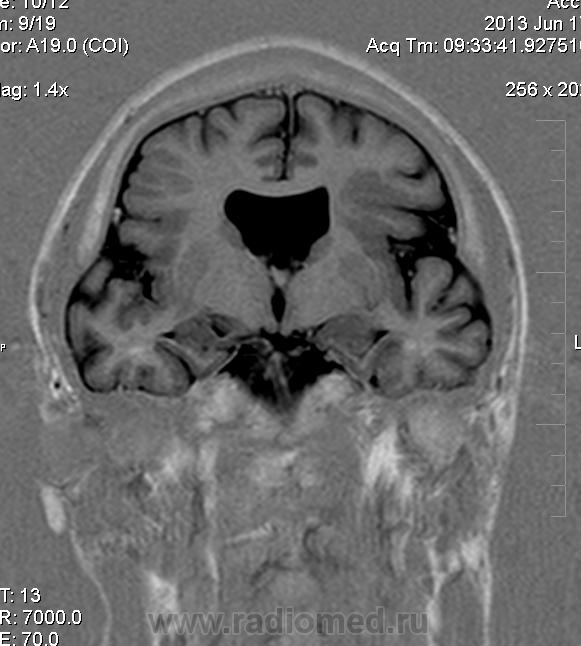

Мужчина 32 лет. Из анамнеза: перинатальное повреждение ЦНС, ДЦП, дизартрия, правосторонний верхний монопарез. С 16 лет приступы эпилепсии.

Аплазия прозрачной перегородки. Шизэнцефалия с открытыми краями в лобно-теменной области слева. Шизэнцефалия с закрытыми краями в лобной области справа? Утолщение коры по контуру расщелин и в области глазничной извилины правой лобной доли. Микрогирия? Гиперостоз костей свода черепа. Уважаемые коллеги, возможно я ошибаюсь, или есть еще аномалия?

Спасибо. Как тогда лучше сформулировать заключение? МР-картина кортикальной дисплазии : двусторнняя шизэнцефалия с утолщением коры по контуру расщелин, микрогирия в лобной области справа, очаг гетеротопии серого вещества в области  глазничной извилины правой лобной доли. Признаки септооптической дисплазии (гипоплазия зрительных нервов, аплазия прозрачной перегородки). Лиссэнцефалии не вижу. Есть сомнения по поводу шизэнцефалии справа (может быть я запуталась в микрогирии и мерещится шизэнцефалия?) Нет ли какой либо анамалии развития черепа?

На мой взгляд, полимикрогирия двусторонняя (конвекситальные отделы дорзальных отделов лобных долей и частично теменных, а также в базальном отделе полюса правой лобной доли) + закрытая шизенцефалия левой лобно-теменной области. Аплазия прозрачной перегородки (как признаки лобарной голопрозенцефалии).